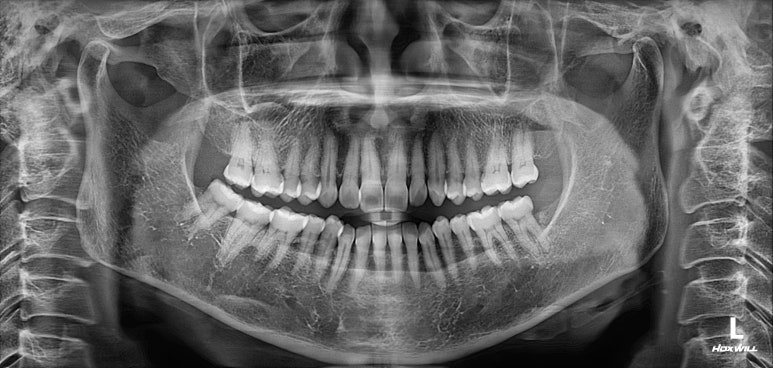

치과용 파노라마 사진을 보았을 때, 전체적으로 건강해보이는 분이었습니다. 건치왕!!!!

치경부 (=치아의 목부분)에 약간의 마모가 되어있는 것이 보이긴 하지만, 충치가 있을 것 같지 않은 분위기..

사람마다 체질이 있듯이, 충치가 잘 생기지 않는 사람이 분명히 있습니다!!

앞니의 치경부 마모가 눈에 띄긴 하지만, 전체적으로 쌓여있는 치석말고는 별 문제가 없었습니다.